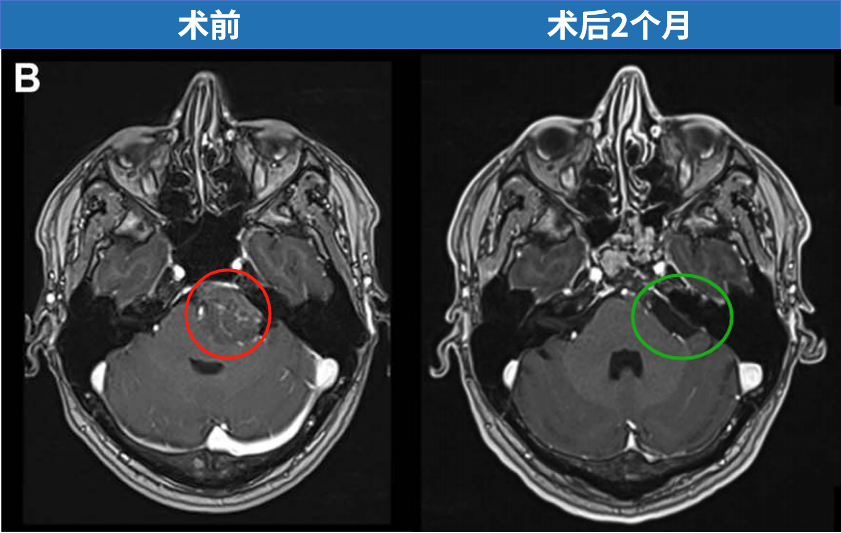

分别在术后 1 周行 CT 及 MRI、2 个月行二次 MRI 复查,结果均提示肿瘤全切除。组织病理学示 WHO I 级。

术后 2 个月 MRI 轴位及矢状位示:脑膜瘤已完全切除,脑干复位良好。